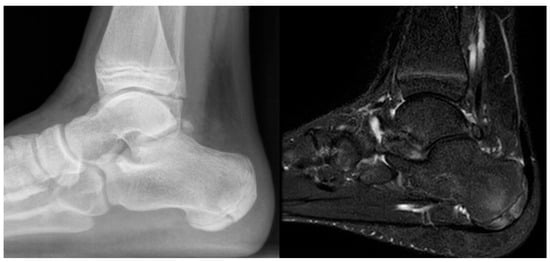

In the later stages, radiographs may reveal characteristic changes including subchondral sclerosis, fragmentation, and flattening of the affected metatarsal head (Figure 10 and Figure 11). In some cases, the presence of joint space narrowing or bony irregularities may also be observed. However, early changes, such as bone marrow edema or subtle cartilage damage, may not be visible on standard radiographs. MRI is particularly useful in the early stages of the disease, as it can detect bone marrow edema, which is a sign of active bone inflammation and necrosis, even before structural changes become apparent on radiographs (Figure 10, Figure 11 and Figure 12).

Figure 10.

Radiograph (left) and MRI (right) of a 17-year-old female patient showing necrotic changes and initial flattening of the second metatarsal head.

Figure 11.

Radiograph (left) and MRI (right) of a 15-year-old male patient with osteochondrosis of the third metatarsal head and early signs of deformation.